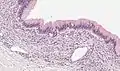

Micrograph showing a mucinous cystadenoma of the ovary. H&E stain.

Mucinous cystadenoma is a benign cystic tumor lined by a mucinous epithelium. It is a type of cystic adenoma (cystadenoma).